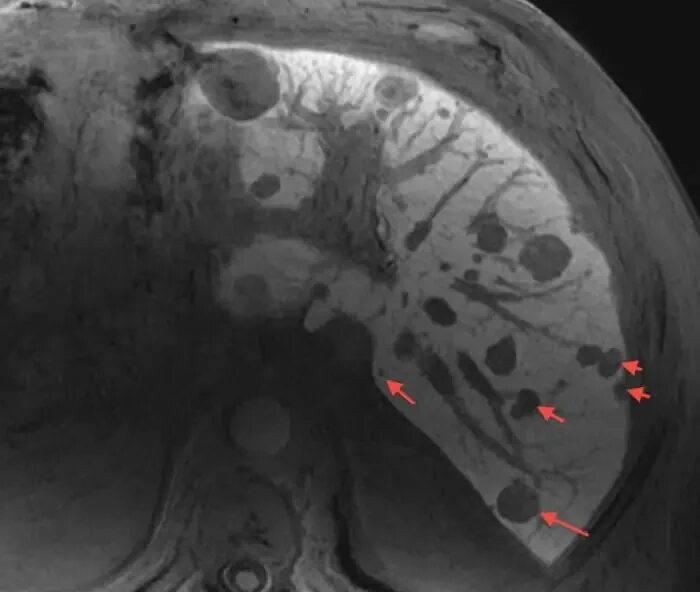

Могут ли метастазы перепутать